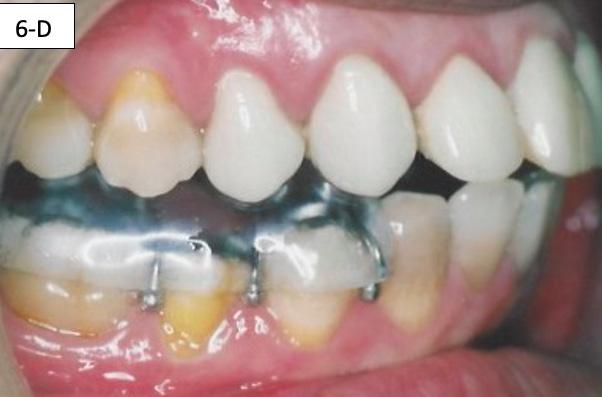

Maxillary and mandibular impressions were taken in irreversible hydrocolloid impression material. Both TMJ discs were recaptured in the Phonetic bite,6 which was recorded with the PVS bite recording material (Blue Bite). The therapeutic splint was fabricated, tried, inserted, and verified that the displaced discs were recaptured. This splint must be worn 24/7, except brushing the teeth, eating and sports (6-A, B, C, D, E).

FIG. 6A: Phonetic bite

FIG. 6B: Therapeutic splint

FIG. 6C: Splint in situ, frontal view

FIG. 6D: Splint in situ, right lateral view

FIG. 6E: Splint in situ, left lateral view